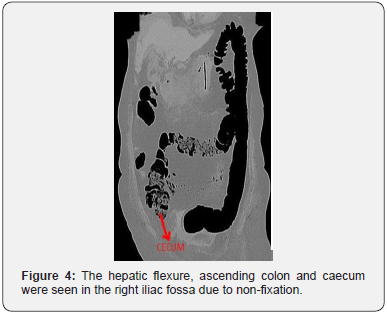

Initial investigations revealed serum amylase 956 IU/L. Her liver enzymes, serum calcium, triglyceride levels were within normal limits. Abdominal ultrasound revealed minimal free fluid abdomen. Pancreas was obscured by bowel gas, gall bladder and common bile duct were normal. CT abdomen demonstrated diffusely enlarged pancreas with shaggy contour and non- enhancing pancreas for more than 30% in the head and proximal body region (Figure 1). Modified CT Severity Index (CTSI) was 8, suggestive of Acute severe Pancreatitis. There was part of the head noted on the right of the second part of duodenum which was continuous with the rest of the pancreas suggestive of Annular Pancreas (Figure 2). The third part of the duodenum was seen anterior to the superior mesenteric artery and transverse colon found to be behind the SMA (Figure 3). The hepatic flexure, ascending colon and caecum were seen in the right iliac fossa due to non fixation, consistent with reverse rotation of the intestine (Figure 4). There were no signs suggestive of pancreatic infection.

RIR is rarest of all rotational abnormalities of the intestine, representing approximately 2-4% of reported cases of malrotation [1]. RIR is due to error in the second stage of midgut rotation. In this anomaly, the gut rotates 90° in a clockwise direction around the axis of the superior mesenteric artery instead of 270° in an anticlockwise direction such that the transverse colon moves to the right behind the superior mesenteric vessels and the duodenum lies anterior to the colon [4]. The rest of the bowel can occupy a normal position but its visceral surface is reversed.